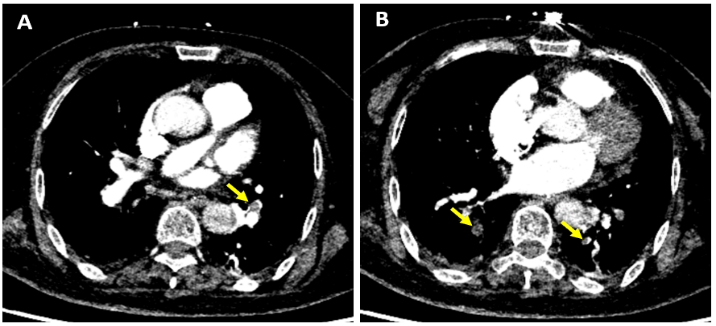

D-二聚体显著升高的A型主动脉夹层一例

病史摘要 52 岁男性患者金某,主因腹痛一周,再发一小时入院。入院前一周排便时出现剑突下疼痛、下颌酸胀、背痛、胸痛,外院考虑急性胆囊炎和骨膜炎,药物治疗后疼痛缓解出院。就诊前一小时,排便时上述症状复发,伴有恶心、出汗、呃逆,自服阿司匹林未缓解。既往有高血压、高胆固醇血症病史。 诊疗过程 患者生命体征平稳,心肺及腹痛查体均阴性。化验显示白细胞升高以中性为主,多项指标轻度异常,D - 二